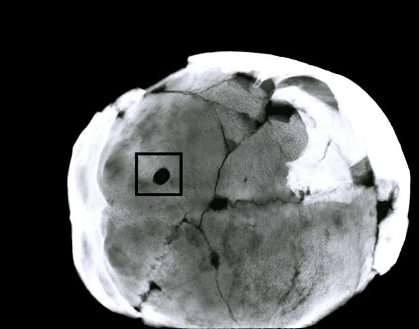

Trephined skull from Acemhöyük -endocranial view

Abstract Trephination is known as one of the oldest forms of brain surgery. It has been identified in the remains from many archaeological sites from the Old and New continents. Anatolia also has several historical stratigraphy and trephination cases that have been described from various time spans and from different locations. Anthropological studies on Anatolian skeletal remains determined that trephination had been practised from Neolithic times to the period of the Ottoman Empire. This paper focuses on one of the ancient brain drilling surgical methods that was discovered on a skull at Acemhöyük, Aksaray-Turkey the site corresponds directly to the Old Assyrian Colony Period in Central Anatolia. Surgery had been performed on the left lambdoid suture of a middle aged female individual. During the first step in macroscopic analysis no significant evidence of healing was observed. However, radiological observation demonstrated that the individual did, indeed, survive for a certain time after the drilling surgery.

(Source: “A middle bronze age case of trephination from central Anatolia, Turkey”, by

Aysen Açıkkol et al., 2009)

Radiograph of Acemhöyük skull from the basal view. Trephination hole lies on the lambdoid